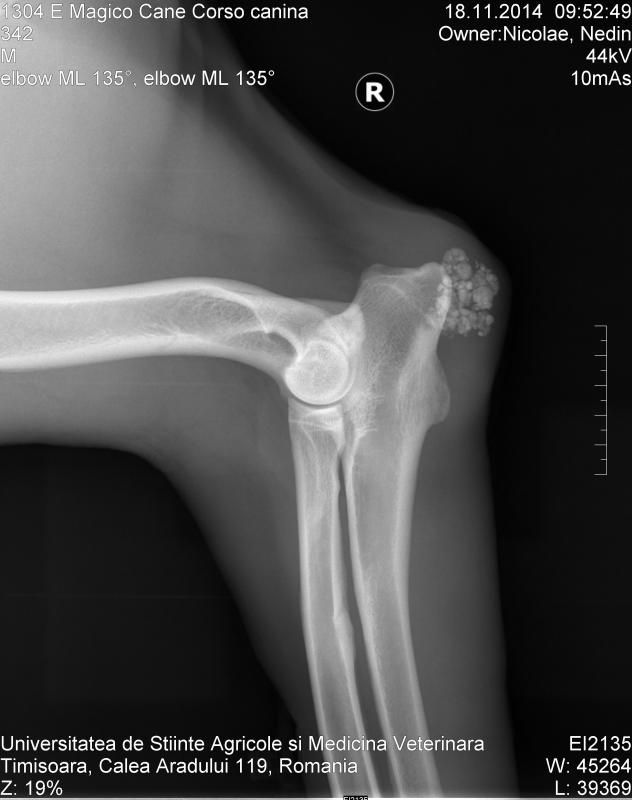

Wat zouden die 'vlokken' kunnen betekenen bij zijn elleboog?

Zouden eeltplekken zo duidelijk zichtbaar zijn op een röntgenopname?laeken schreef:Die hond ligt op harde ondergrond en die vlokken zijn zover ik kan bedenken dus eeltplekken van het liggen.

Maar daarom moet er dus gevoeld worden, aan de foto alleen heb je niks eigenlijk. En theoretisch moet het te voelen zijnInge O schreef:ja, klopt, het feit alleen dat het harde hoorn is maakt het nog niet zichtbaar op rx - een gecalcificeerde slijmbeurs op die plaats zou eventueel ook kunnen?Jeannettebo schreef:eigelijk zou het dan gecalcificeerd moeten zijn, wil het net zo wit tonen als bot.

ik zie in ieder geval geen relatie met het bot/gewricht.

Onderhuids? Zo ziet het er mi uit.laeken schreef:Die hond ligt op harde ondergrond en die vlokken zijn zover ik kan bedenken dus eeltplekken van het liggen.

Dat denk ik dus niet.. Tenzij ze gecalcificeerd zijn. Het ziet eruit als iets met kalkafzetting. Hoe dik de hoornlaag ook is, dat geeft niet dit beeld voor zover ik weet.Tara schreef:Dat was ook het eerste dat in mij opkwam, en ik denk inderdaad dat je dat op de foto goed kunt zien.laeken schreef:Die hond ligt op harde ondergrond en die vlokken zijn zover ik kan bedenken dus eeltplekken van het liggen.

Mooi om te zien!Inge O schreef:nee, zeker niet, zo ziet de hoef van een paard eruit op rxJeannettebo schreef:Dat denk ik dus niet.. Tenzij ze gecalcificeerd zijn. Het ziet eruit als iets met kalkafzetting. Hoe dik de hoornlaag ook is, dat geeft niet dit beeld voor zover ik weet.Tara schreef:Dat was ook het eerste dat in mij opkwam, en ik denk inderdaad dat je dat op de foto goed kunt zien.laeken schreef:Die hond ligt op harde ondergrond en die vlokken zijn zover ik kan bedenken dus eeltplekken van het liggen.